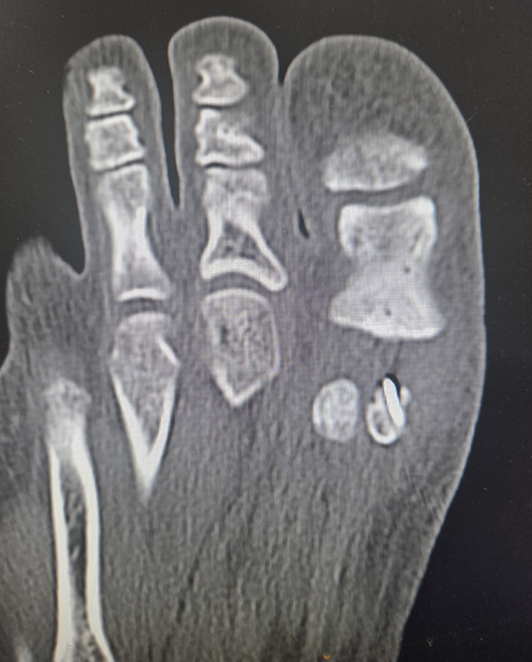

하지만 증상이 계속 악화되고 있다는 점, 그리고 이분 종자골을 가진 사람도 사이 연골 결합이 손상되면 골절과 같은 양상의 통증을 느낄 수 있다는 점에 주목했다. 나는 환자에게 '종자골 골절'의 가능성을 설명하고 CT와 MRI 등 정밀 검사를 진행했다.

image.png

정밀 검사에서도 명확한 골절 소견은 나오지 않았다. 이때부터 깊은 고민이 시작됐다. 안전하게 '종자골염'으로 진단하고 지켜볼 수도 있었지만, 이미 6개월간의 보존적 치료에 실패한 상태였다. 결국 경험에 비추어 가장 확률 높은 진단을 추려야 했다. 사실 종자골 골절은 발생 빈도가 매우 낮은 희귀 질환이라 확진을 내리는 것 자체가 조심스러운 일이다.